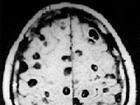

放射冠区腔隙性脑梗死在临床上较为常见,是脑梗塞(脑血栓、 脑栓塞、 腔隙性脑梗塞、 多发性脑梗塞、 短暂性脑缺血爆发)的一种症型,放射冠是大脑解... 2、糖尿病患者要严酷节制饮食,降糖医治,使血糖节制在一般范畴,糖尿病患者血压应节制在≤130/85mmHg; 3、高血脂患者应进行降脂医治; 4、按期...